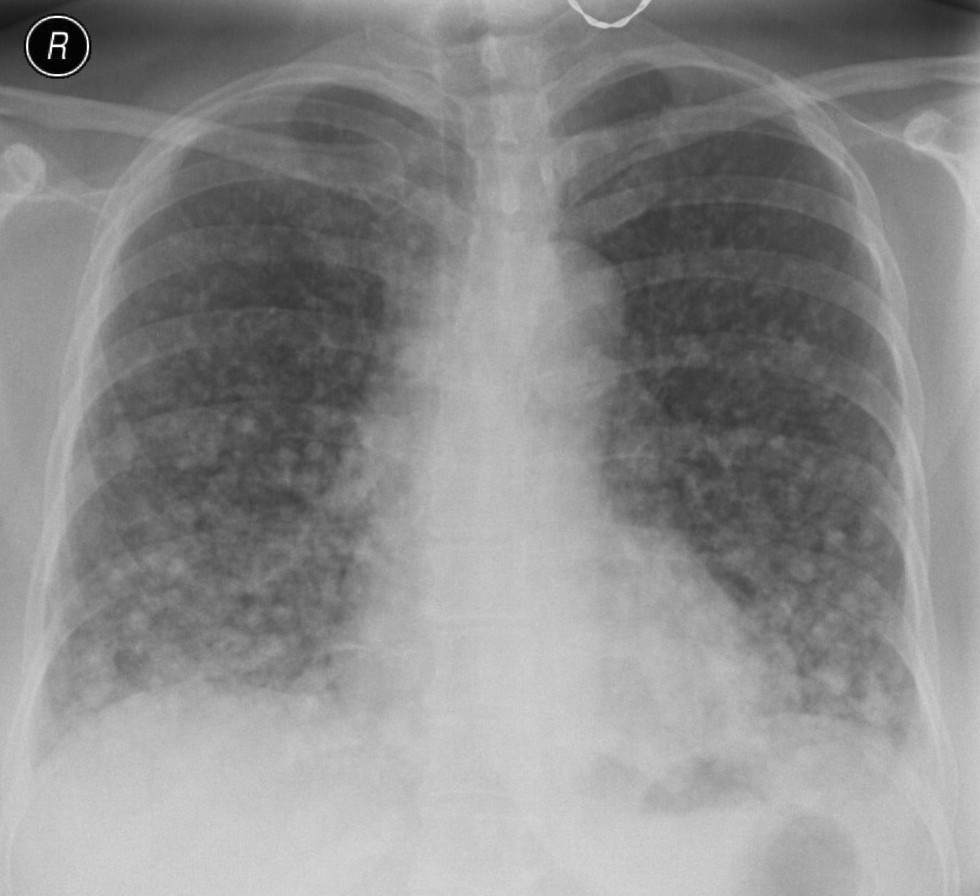

Unklare verdichtungen der lunge links. CAS Article PubMed Google Scholar. Die konventionelle Röntgenaufnahme der Lunge zeigte bipulmonale laterale Verschattungen verdächtig auf das Vorliegen einer atypischen Pneumonie Abb1. Neben der Lungenfunktionsprüfung werden zur Diagnose einer Lungenfibrose bildgebende Verfahren angewandt.

Verdacht auf Erkrankungen der Bronchien der Lunge der Pleura der Thoraxwand des Atemantriebs und der Atemmuskulatur. Neben der Lungenfunktionsprüfung werden zur Diagnose einer Lungenfibrose bildgebende Verfahren angewandt. Krankheiten die sich in den Alveolen dem terminalen Luftraum der Lunge abspielen haben ein anderes radiologisches Bild als solche die im Interstitium der Lunge lokalisiert sind. Verdichtung Röntgen Lunge. Die betroffenen Bereiche der Lunge sehen dann auf den CT-Bildern heller aus als das gesunde Lungengewebe. Wenn die hellen Stellen in der Lunge die Form eines Streifens haben dann sagt der Arzt dazu streifige Verdichtung. Es wird meist in der Neonatalperiode diagnostiziert und manifestiert sich klinisch in einer unterschiedlich ausgeprägten Tachypnoe. Die optimale Perfusions- und Ventilationsverteilung an dieser komplexen Oberflächenstruktur ist Voraussetzung für deren Diffusionseigenschaften Abb. Schranz Kinderherzzentrum der Universität Gießen danken.

Daher ist die linke Lunge viel kleiner als die rechte Lunge das Herz nimmt den Raum auf der linken Seite ein. Störungen des Gasaustausches. Bei manchen Erkrankungen oder Veränderungen lässt die Lunge die Röntgenstrahlung weniger gut durch als normal. Pneumologische Leitsymptome Atemnot Husten Auswurf. Außerdem liefert sie die Basis für die Entscheidung zu bildgebenden Verlaufsbeobachtungen. Nun habe ich unheimliche Angst das sich der Verdacht bestätigt. Dieser medizinische Begriff wurde für Sie übersetzt von.